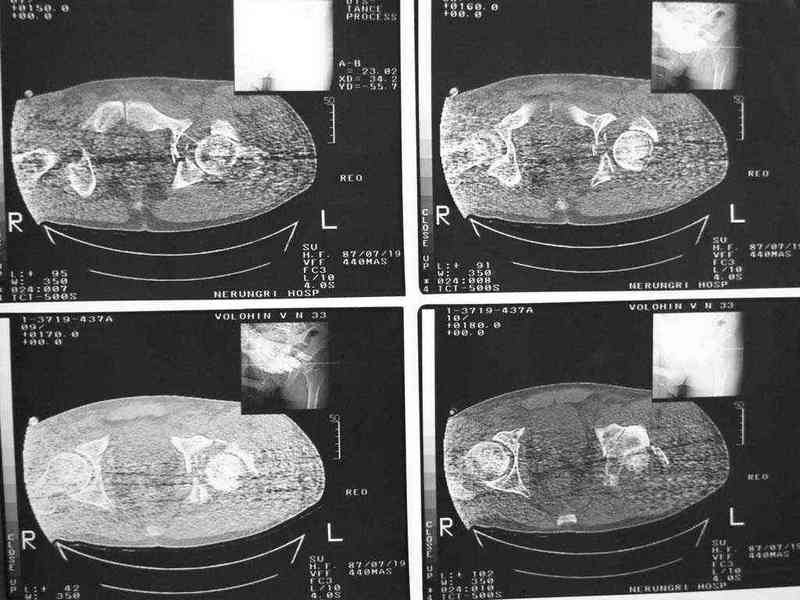

еще одно дополнение

|